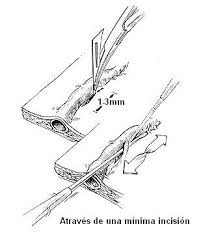

329 × 361 - gimolimpo.com

{"cb":3,"cl":9,"cr":9,"ct":3,"id":"xpk45dB8E7I8sM:","isu":"gimolimpo.com","itg":0,"ity":"jpg","oh":361,"ou":"http://www.gimolimpo.com/Paginas/feblectomia_archivos/image007.jpg","ow":329,"pt":"FEBLECTOMIA","rid":"ZemkA-aU5uHAnM","rmt":0,"rt":0,"ru":"http://www.gimolimpo.com/Paginas/feblectomia.htm","s":"óptima

relación

379 × 281 - gimolimpo.com

{"id":"yi_QeHfQlQD5hM:","isu":"gimolimpo.com","itg":0,"ity":"jpg","oh":281,"ou":"http://www.gimolimpo.com/Paginas/feblectomia_archivos/image003.jpg","ow":379,"pt":"FEBLECTOMIA","rid":"ZemkA-aU5uHAnM","rmt":0,"rt":0,"ru":"http://www.gimolimpo.com/Paginas/feblectomia.htm","s":"Tipos

de

tratamiento","sc":1,"st":"Olimpo","th":193,"tu":"https://encrypted-tbn0.gstatic.com/images?q\u003dtbn:ANd9GcTl_DJI550zaYSZMH-miDVhWY4UK03LOi9ze-1B_FsuneyxG_grOQ","tw":261}

231 × 397 - gimolimpo.com

{"cl":3,"id":"Ofxp5Rburirp3M:","isu":"gimolimpo.com","itg":0,"ity":"jpg","oh":397,"ou":"http://www.gimolimpo.com/Paginas/feblectomia_archivos/image005.jpg","ow":231,"pt":"FEBLECTOMIA","rid":"ZemkA-aU5uHAnM","rmt":0,"rt":0,"ru":"http://www.gimolimpo.com/Paginas/feblectomia.htm","s":"Flebectomía

ambulatoria, es la safenectomía, modificada por el Dr. Oesch, suizo,

que consiste en efectuar la exéresis de la vena, sin lesionar los

tejidos

...","sc":1,"st":"Olimpo","th":294,"tu":"https://encrypted-tbn0.gstatic.com/images?q\u003dtbn:ANd9GcQTaZ5oRKfEvwuBOC5RWCE4GIQU2e4MrfYhpJMx2vBMlbt5qVXNew","tw":171}